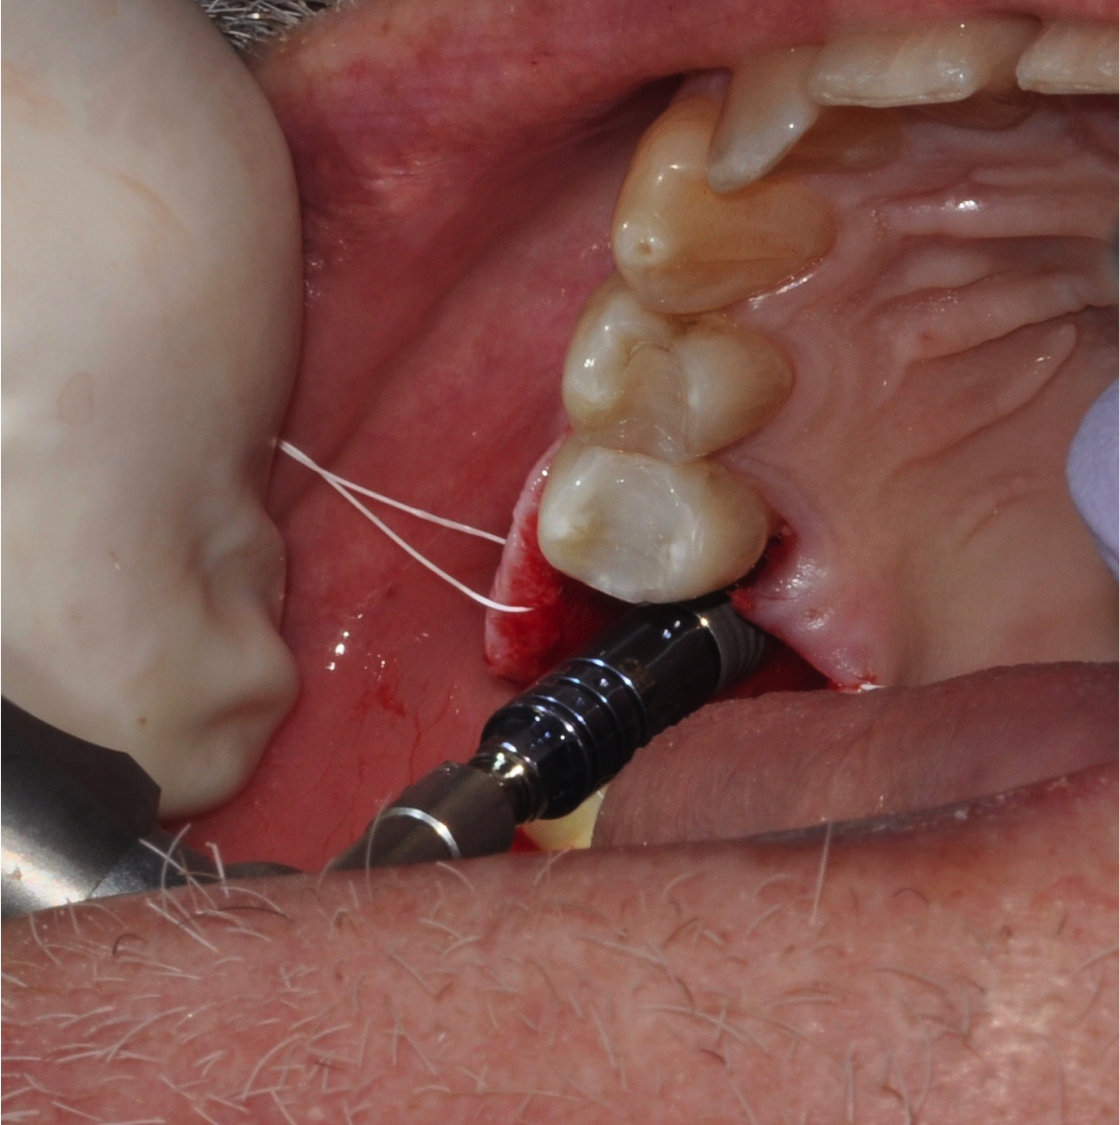

For the surgery, a crestal incision was made, and a flap was reflected to the subperiosteal area to expose the bone. Because of the tight, firm quality of the gingiva, a suture was placed both lingually and buccally to pull the tissue out and ensure that it would not get caught underneath the surgical guide and compromise proper seating. Following the guided surgical procedure, the recommended drilling series was followed to create the osteotomy and insert the implant (Figure 17 and Figure 18), and a postoperative radiograph was taken (Figure 19). A cover screw was attached to the implant, and the flap was sutured over it. The patient was allowed to heal with the implant submerged for 4 months.

Fig 17. Suture to pull tissue out to help ensure proper seating.

Figure 17